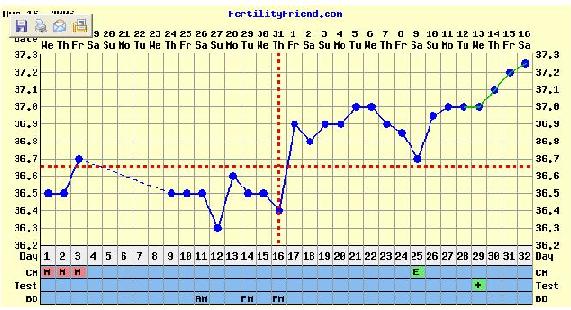

Holnap majd jövök az ideillő görbémmel